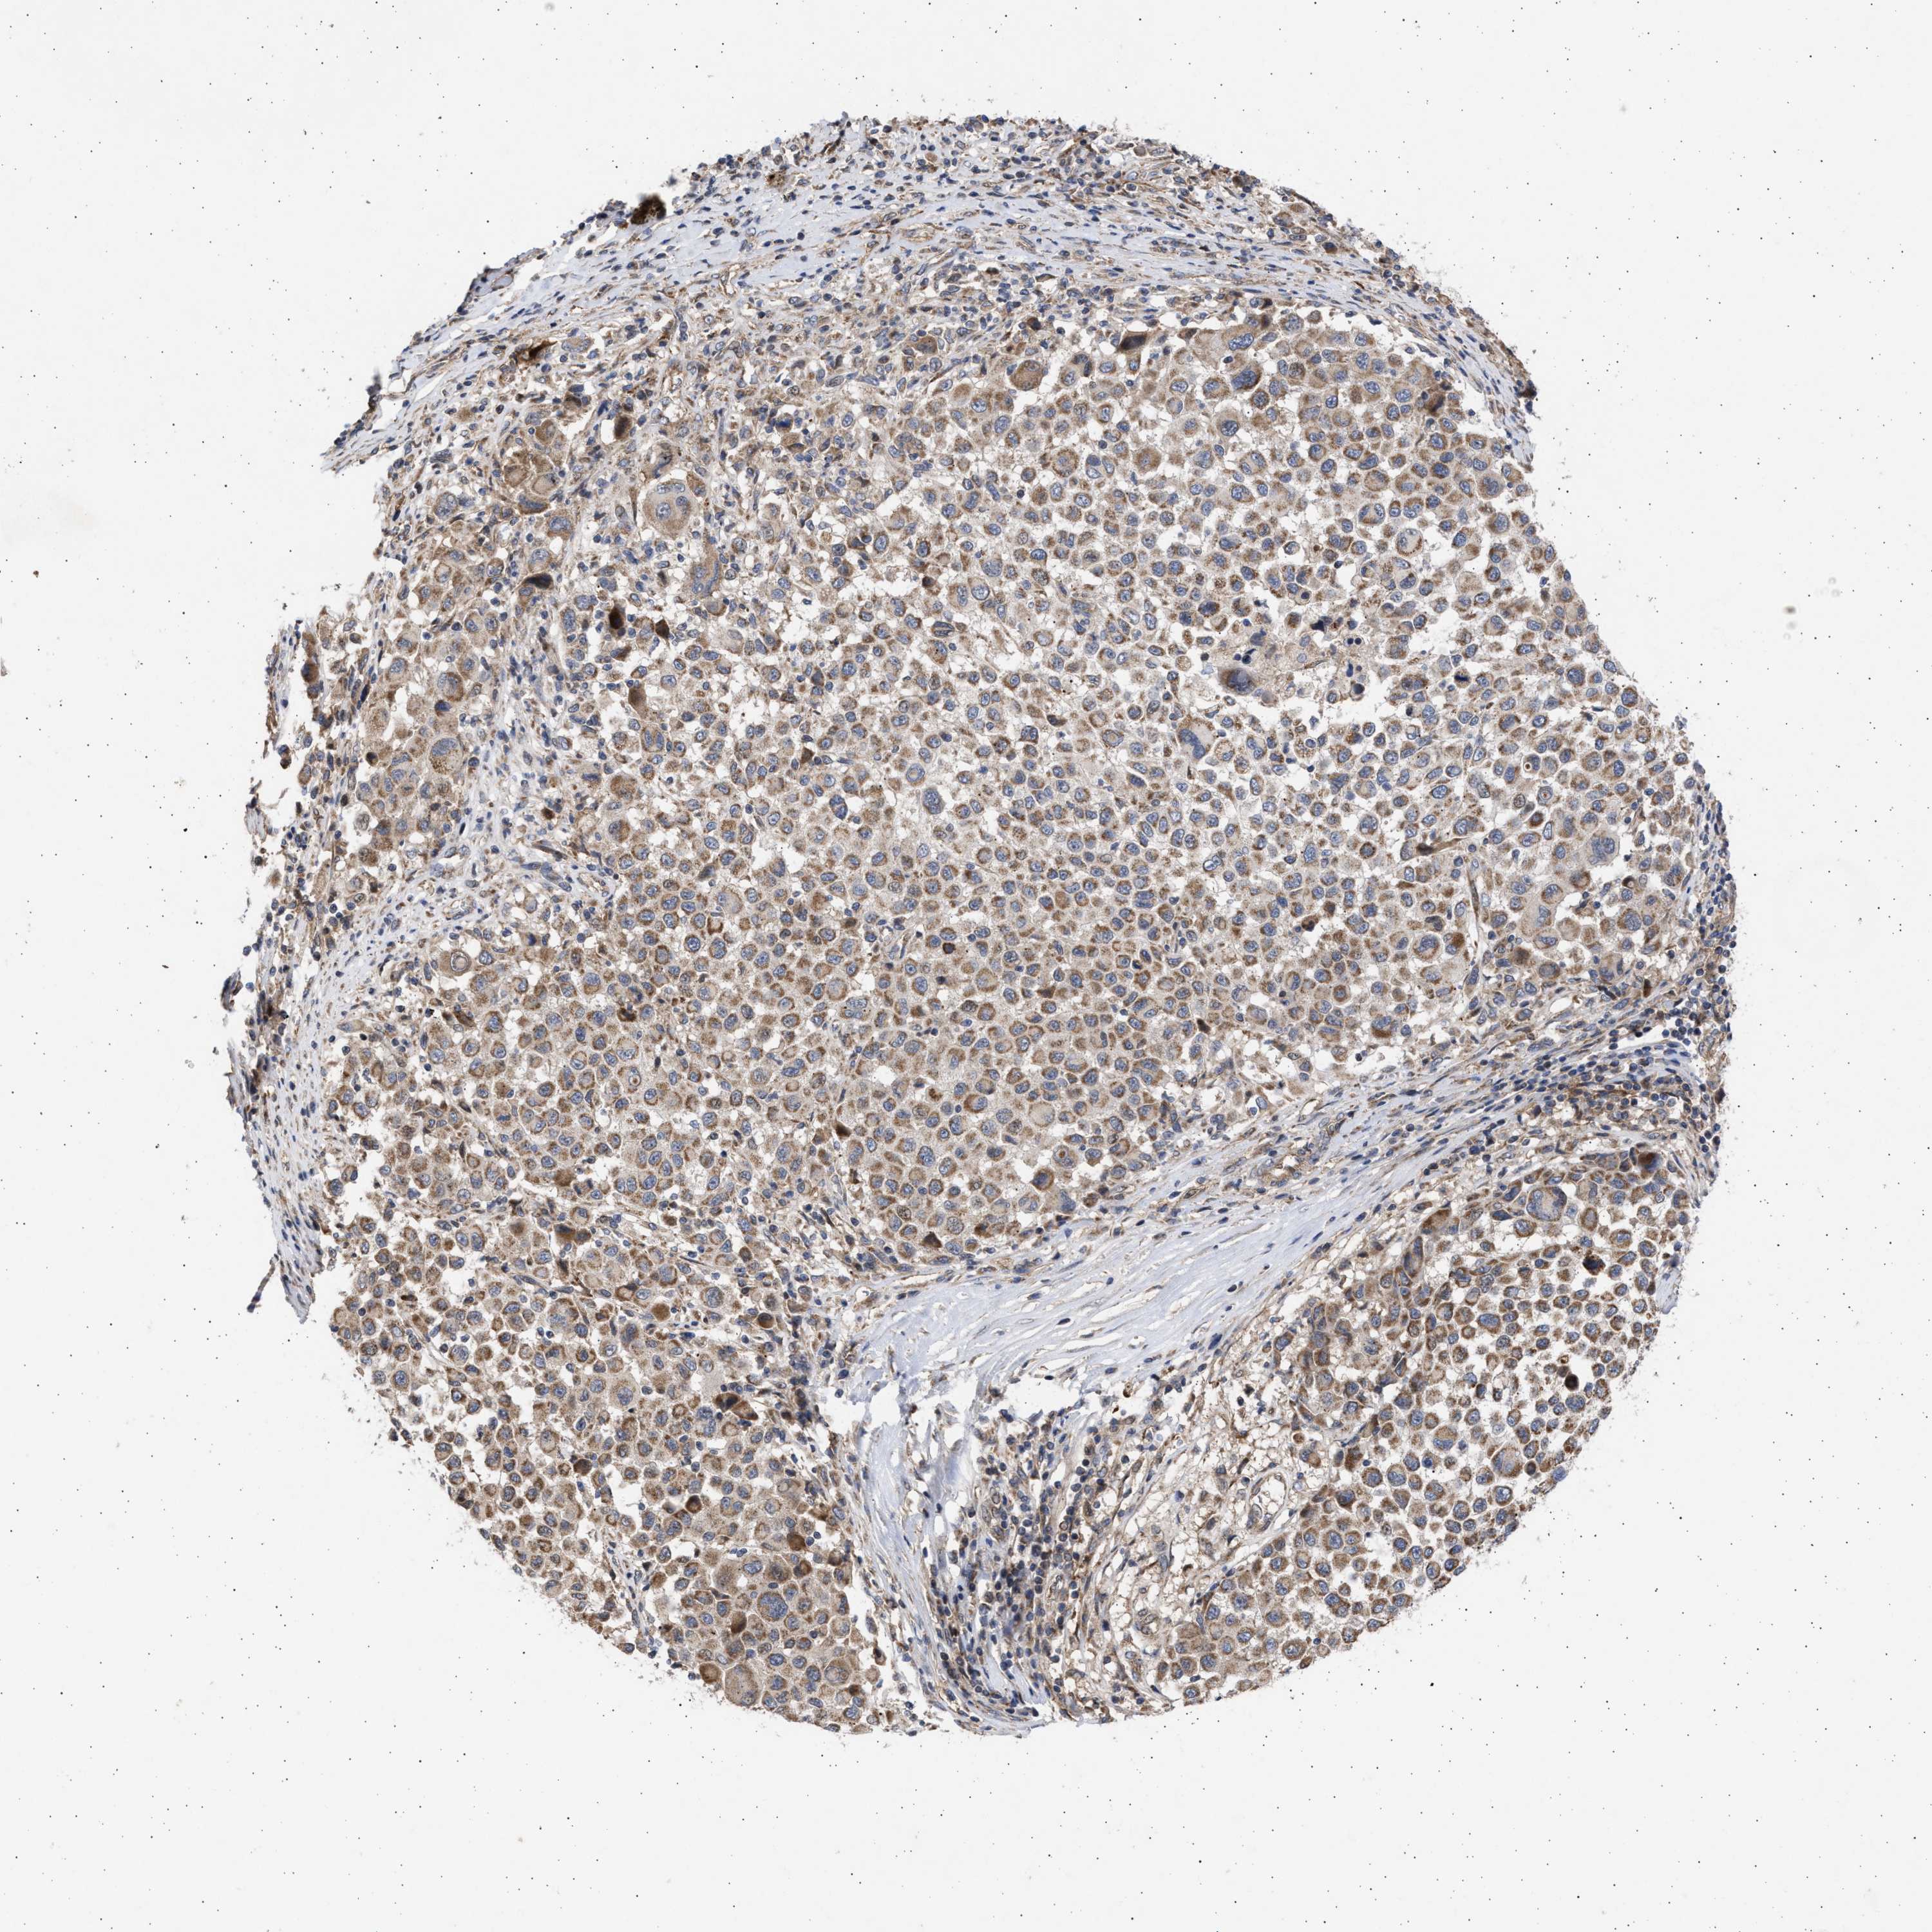

MELANOMA - Protein expressioni

A mouse-over function shows sample information and annotation data. Click on an image to view it in a full screen mode. Samples can be filtered based on level of antibody staining by selecting one or several of the following categories: high, medium, low and not detected. The assay and annotation is described here.

Note that samples used for immunohistochemistry by the Human Protein Atlas do not correspond to samples in the TCGA dataset.

Antibody stainingi

Antibody staining in the annotated cell types in the current human tissue is reported as not detected, low, medium, or high, based on conventional immunohistochemistry profiling in selected tissues. This score is based on the combination of the staining intensity and fraction of stained cells.

Each image is clickable and will lead to virtual microscopy that enables deeper exploration of all samples and also displays staining intensity scores, fraction scores and subcellular localization as well as patient and tissue information for each sample.

Antibody HPA023010

Antibody HPA052380

Staining

High

Medium

Low

Not detected

Intensity

Strong

Moderate

Weak

Negative

Quantity

>75%

75%-25%

<25%

None

Location

Nuclear

Cytoplasmic/membranous

Cytoplasmic/membranous,nuclear

Malignant melanoma, NOS

Malignant melanoma, Metastatic site